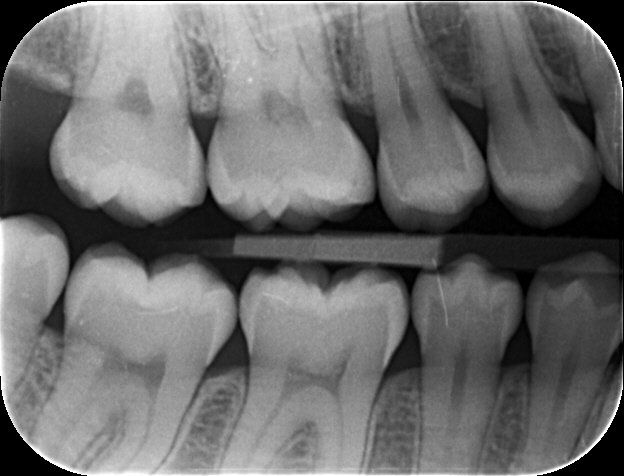

Digital X-Rays are as comfortable as normal x-rays, but the benefits are that you receive a significantly reduced dose of radiation. In addition to this, enlarged images of these x-rays are available for viewing almost immediately after they have been taken.

Are x-rays really necessary? The short answer is YES. Concerns about radiation are common and quite understandable. However, a full series of dental x-rays exposes you to less radiation than a flight on a typical commercial airliner. Digital x-rays reduce the dosage of radiation even further!

The reasons we need dental x-rays:

Evaluating bone support around teeth and gum disease.

Discovering abscesses and root infections.

Discovering cysts and tumours.

Monitoring any progress/lack of progress of any lesions.